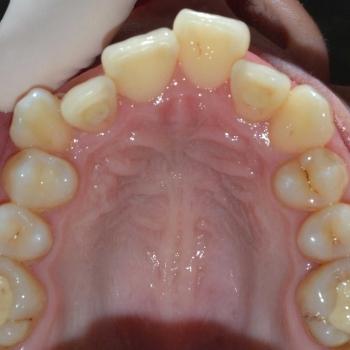

Tünde a felső fogív torlódása, illetve az alsó metszőfogak között található rések miatt keresett fel. Az első találkozásunk alkalmával azonban fény derült a középvonalak eltolódására, enyhe mélyharapásra, a felső metszőfogak túlzott elülső pozíciójára, illetve a régóta hiányzó alsó 6-os fog helyének beszűkülésére is, így a kezelési terv ezen problémák megoldására is kitért.

Tünde végül úgy döntött, hogy nem csak az esztétikai, de a funkciós problémák is szeretné megoldani, melyhez hagyományos fém fogszabályozót választott. A fogszabályozáshoz különböző kiegészítőket is igénybe vettünk úgy, mint harapásemelő, különböző intermaxillaris gumihúzások, illetve egy speciális szájpadi mini-implantátum a hozzá kapcsolódó transpalatinalis ívvel (hibrid transpalatinal ív), ami minimalizálta a hátsó fogak mozgását, miközben a felső metszőfogak hátrafele mozogtak.

A kezelés végére minden problémát sikerült megoldanunk, a középvonalak korrekcióját leszámítva. Ennek ellenére, mivel a felső középvonal az arc tengelyében helyezkedik el, az esztétikai eredmény nem csorbult és a funkciót sem befolyásolta. A jobb alsó 6-os fog implantációs pótlása a fogszabályozás befejeztével kezdődött meg.